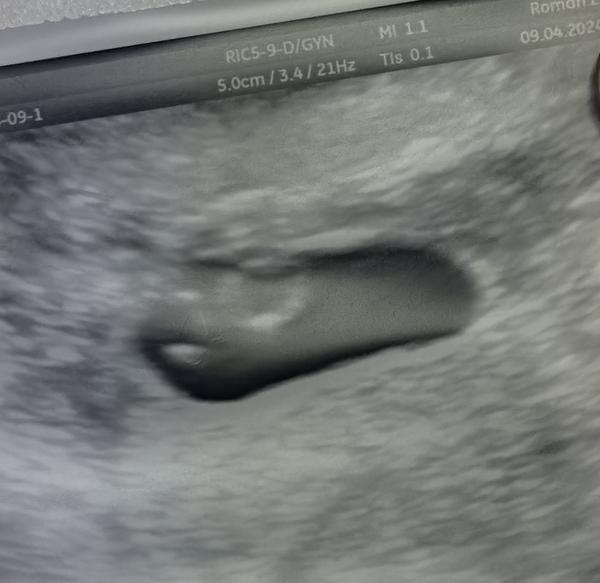

Bola som u lekára a na ultrazvuku mi povedal, že môžu to byt dvojičky, ale nie je iste či obidva prežijú. Ale keď sa pozerám na to, zdá sa mi že sú veľmi blízko vedľa seba, u koho bola podobná situácia, ako ste dopadli? Dakujem